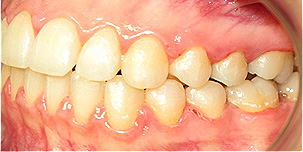

Apinhamento dentário com os dentes caninos em desoclusão (classe II, divisão 2).

![]() |

Após dois anos de tratamento ortodôntico.